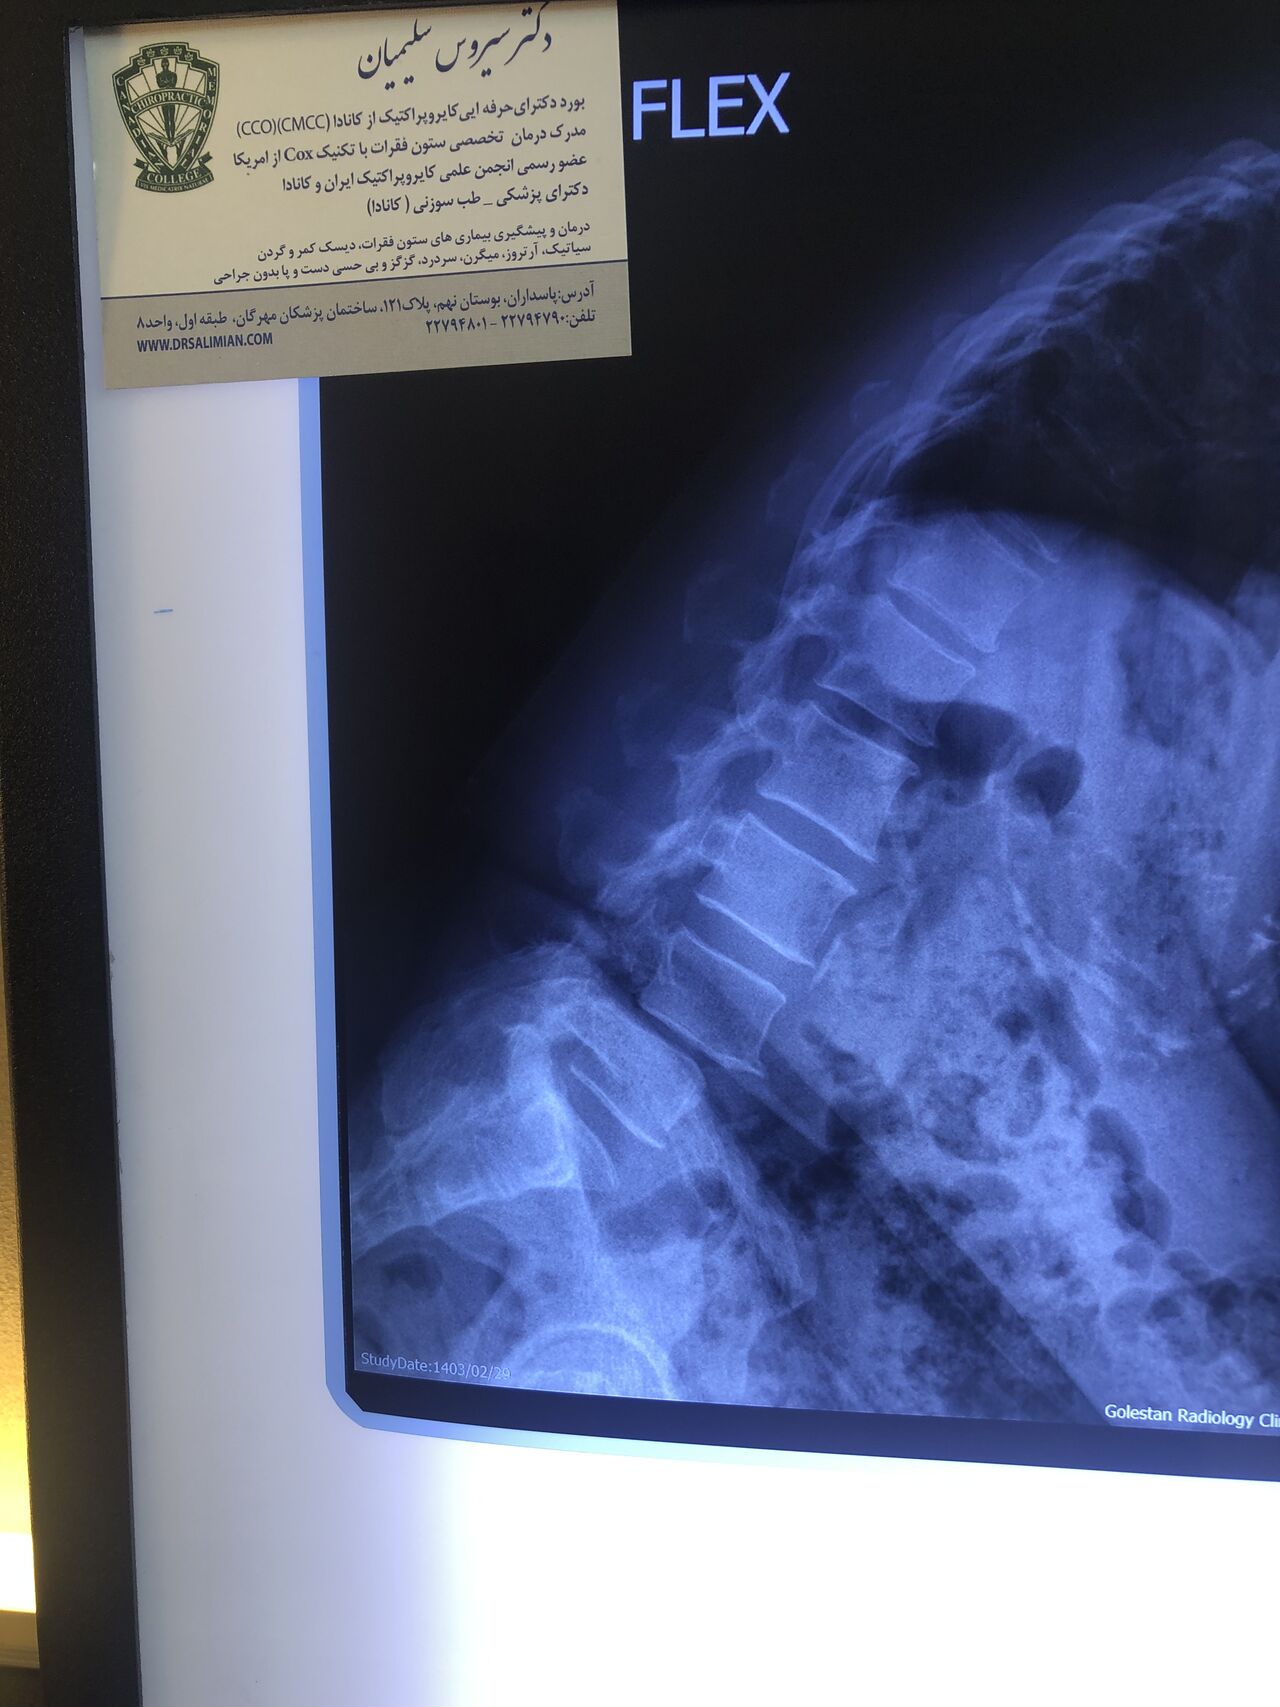

Since I’ve noticed instability in some segments I asked for dynamic L/S x ray:we see mild L4 ant listens due to DjD/DDD. There is not any pars defect.